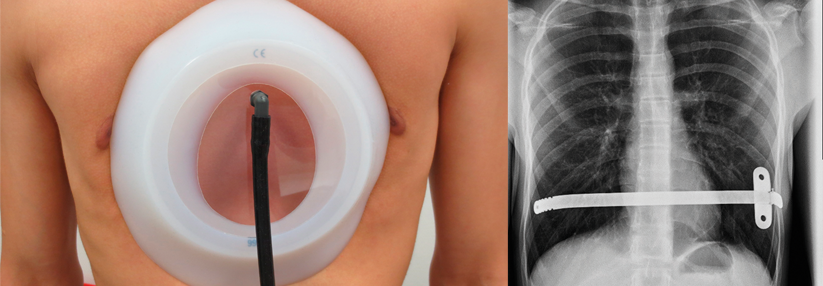

Gute Anhaltspunkte für die Wahrscheinlichkeit eines pCR nach neoadjuvanter Therapie könnten zukünftig die tumorinfiltrierenden Lymphozyten (TIL) und eine hohe Aufnahme von [18F]-2-Fluor-2-desoxy-D-glucose (18F-FDG) in der PET-CT* bieten. Wie Prof. Hatschek erklärte, korrelierten ≥ 10 % TIL in der Basisuntersuchung mit einem signifikant höheren pCR-Anteil im Vergleich zu Werten < 10 % (52,2 % vs. 30,4 %). Patientinnen, die nach zwei Behandlungszyklen einen frühen Abfall der 18F-FDG-Aufnahme im PET-CT von mehr als 75 % zeigten, erreichten zu 70,3 % ein pCR, die übrigen nur zu 22,5 %.

Beide Biomarker sind laut Professor Dr. Valentina Guarneri von der Universität Padua Erfolg versprechend. Das PET-CT sei aber noch nicht reif für die Routine, erklärte sie in der Diskussion der Studie. Die Analyse und Dokumentation der TIL werde dagegen bereits in vielen Leitlinien empfohlen. Prof. Hatschek stellte auch erste Ergebnisse zum ereignisfreien Überleben vor. Nach median 28,5 Monaten Beobachtungszeit fand sich bislang kein Unterschied in den Armen Trastuzumab Emtansin vs. Docetaxel, Trastuzumab und Pertuzumab. Allerdings war die Zahl der Ereignisse auch noch sehr gering.